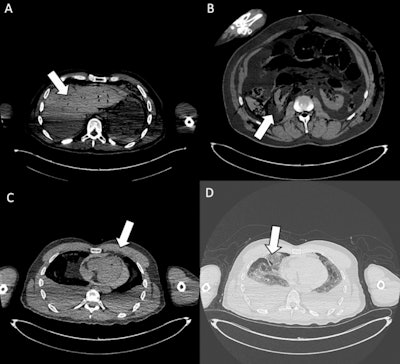

Exit wounds. (A) Axial CT scan shows an exit wound in the subcutaneous soft tissues at the root of the right thigh (white arrow). (B) Axial CT image depicts an exit wound in the left supraclavicular region (white arrow), visible as a focal soft-tissue defect with surrounding gas bubbles. (C) Cross-sectional CT slice illustrates an exit wound at the left posterior abdominal wall (white arrow), with subcutaneous emphysema and adjacent soft-tissue disruption. (D) CT image demonstrates an exit wound in the right chest region (white arrow), characterized by soft-tissue laceration and subcutaneous gas. Exit gunshot wounds were associated with the lowest inter-reader agreement (Fleiss’ kappa = 0.36). Despite the very high specificity of virtopsy, sensitivity was particularly low among readers without forensic experience (12.5% and 16.7%), underlining the difficulty in correctly identifying these injuries on postmortem CT.